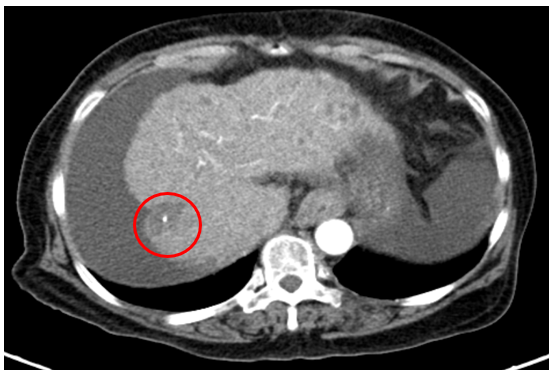

Chụp cắt lớp vi tính ổ bụng

Gan: biến đổi hình thái, bờ không đều. Nhu mô gan phải có khối giảm tỉ trọng kích thước 26x25mm, ranh giới không rõ, co kéo bao gan lân cận, trong có hình ảnh tăng tỉ trọng của vật liệu nút mạch, sau tiêm có phần ngấm thuốc ngấm thuốc.

Dịch quanh gan 8mm., dịch tự do ổ bụng

àHình ảnh u gan phải sau điều trị hiện còn phần ngấm thuốc (Vòng tròn đỏ) /Xơ gan